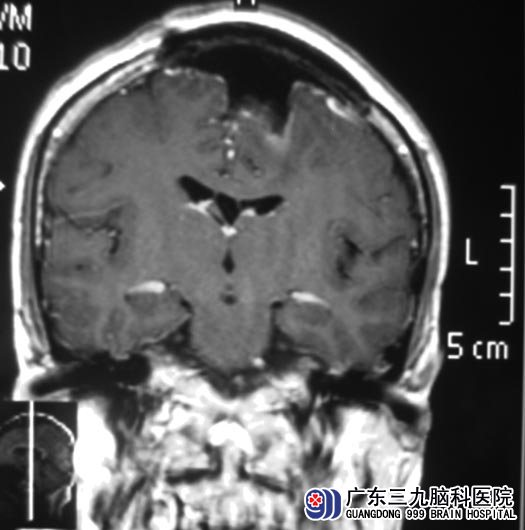

5月30日,综合神经外科 鲁明主任主刀。术中见颅骨突起部分骨质发白并有破坏,显微镜下见肿瘤呈黄色、质软、血供丰富、边缘尚清,肿瘤主体位于镰窦左侧,沿矢状窦向右侧脑表面生长,使用超生吸引切除部分肿瘤,沿大脑镰肿瘤基底部,剪除大脑镰,分离肿瘤边界,保护脑组织,完整切除肿瘤,切除大小约4cm×4.5cm×4.5cm,达辛普森I级切除,清除颅骨内坏死肿瘤组织,还纳骨瓣固定,手术顺利。术后杨老伯未出现功能障碍的损害,病理结果为:脑膜瘤(过度型,WHO I级)。

▲手术后